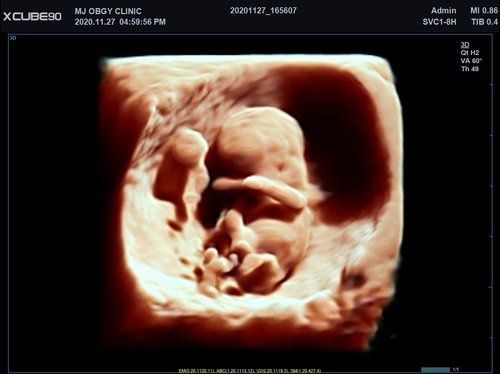

Mit dem X-CUBE 90 beginnt ALPINION eine neue Generation an Farbdopplersystemen, die X- CUBE Serie. Mit Bildverarbeitungstechnologien eines Premiumsystems und neuen Breitband- Schallköpfen mit X + Crystal Signature™ Technologie wartet das neue X-CUBE 90 auf.

Neben der hohen Bildqualität liegt ein weiterer Fokus auf der Vereinfachung und der Anpassung der Bedienung des Ultraschallgeräts. Individuell programmierbare Workflows und ein erweitertes Spektrum an automatisierten Messungen ermöglichen ein schnelleres und genaueres Arbeiten in jeder Situation.

X + Architecture

Die X + Architecture ist eine erstklassige Imaging-Plattform, die durch die Kombination von X + Crystal Signature™, der Schallkopftechnologie mit hoher Sensitivität und Breitbandigkeit, und X + FIT, ALPINIONs modernste Beamforming- und Datenverarbeitungstechnologiengeschaffen wurde. X + FIT ist eine neue Technologie, die den Schallstrahl scharf fokussiert sendet, ein großes Datenvolumen empfängt und mit hoher Geschwindigkeit verarbeitet. Darüber hinaus nutzt X + Crystal Signature™ Einkristalle und unser eigenes entwickeltes Schallkopfmaterial, um eine hervorragende Brillanz zu erzielen und die Diagnosemöglichkeiten zu erweitern.

• SVC1-8H (1-8 MHz) für Ultraschalluntersuchungen in Bereichen Abdomen, Geburtshilfe, Gynäkologie, Urologie, Pädiatrie, EM